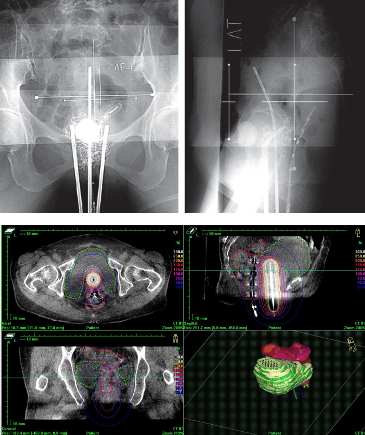

従来は2方向からのレントゲン撮影による2次元治療計画が行われていましたが、現在、当院ではアプリケーターを挿入したままCT画像を撮影できます。この画像を使って、3次元治療計画を行うI G B Tを実施しています。

レントゲンよりも臓器が見えるため、腫瘍にしっかりと放射線を照射しながら、正常臓器の線量を低減することが可能です。